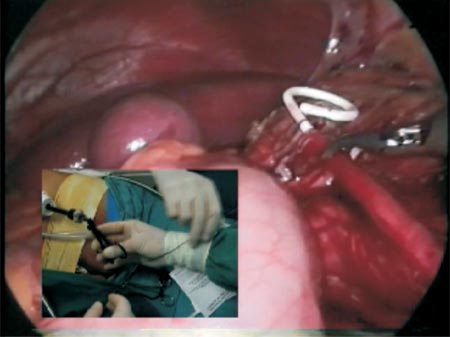

After the section of the stenosed area, the ureter spatulation (Photo 5) and the completion of the posterior wall anastomosis (Photo 6), the Levine catheter is disconnected from the ureteral catheter and a retrograde hydrophilic guidewire is inserted through the external orifice of the ureteral catheter which will be exposed by the left hand trocar (Photo 7 and Figure 5) with care in order to avoid the anastomosis posterior stitches to tear (during this manipulation if possible an atraumatic forceps should be maintained).

Photo 7 - Retrograde passage of the guidewire guided by an atraumatic forceps outside the left hand port.

Figure 5 - Diagrammatic representation of the retrograde passage of the guidewire.